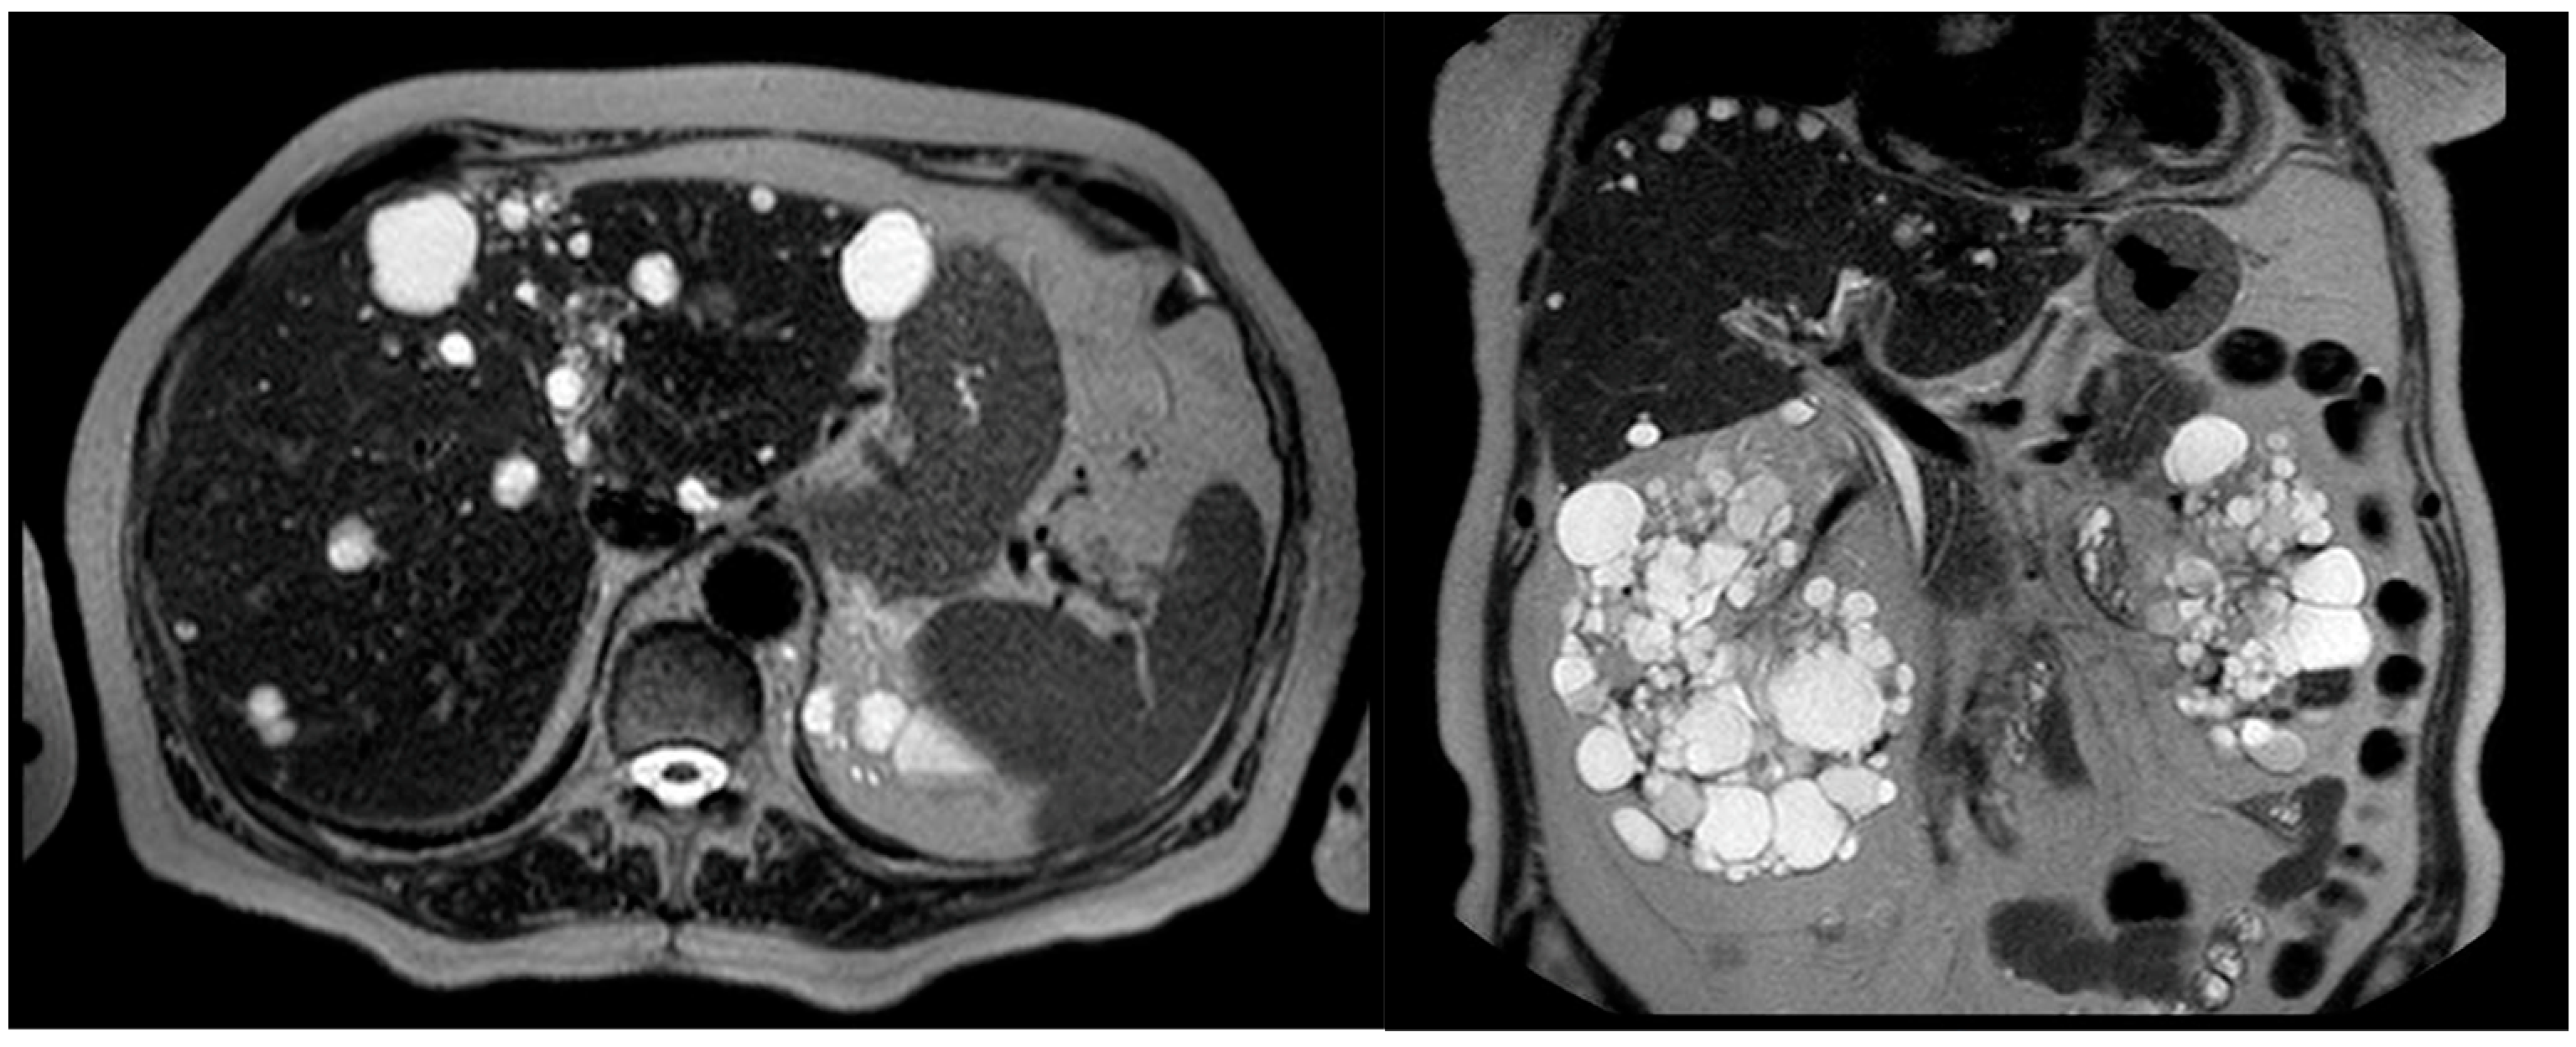

- Hogan, M.C.; Abebe, K.; Torres, V.E.; Chapman, A.B.; Bae, K.T.; Tao, C.; Sun, H.; Perrone, R.D.; Steinman, T.I.; Braun, W.; et al. Liver involvement in early autosomal-dominant polycystic kidney disease. Clin. Gastroenterol. Hepatol. 2015, 13, 155–164.e6. [Google Scholar] [CrossRef] [PubMed]

- Bae, K.T.; Zhu, F.; Chapman, A.B.; Torres, V.E.; Grantham, J.J.; Guay-Woodford, L.M.; Baumgarten, D.A.; King, B.F., Jr.; Wetzel, L.H.; Kenney, P.J.; et al. Magnetic resonance imaging evaluation of hepatic cysts in early autosomal-dominant polycystic kidney disease: The Consortium for Radiologic Imaging Studies of Polycystic Kidney Disease cohort. Clin. J. Am. Soc. Nephrol. 2006, 1, 64–69. [Google Scholar] [CrossRef]

- Gabow, P.A.; Johnson, A.M.; Kaehny, W.D.; Manco-Johnson, M.L.; Duley, I.T.; Everson, G.T. Risk factors for the development of hepatic cysts in autosomal dominant polycystic kidney disease. Hepatology 1990, 11, 1033–1037. [Google Scholar] [CrossRef]

- van Aerts, R.M.; Kievit, W.; de Jong, M.E.; Ahn, C.; Bañales, J.M.; Reiterová, J.; Nevens, F.; Drenth, J.P. Severity in polycystic liver disease is associated with aetiology and female gender: Results of the International PLD Registry. Liver Int. 2019, 39, 575–582. [Google Scholar] [CrossRef]